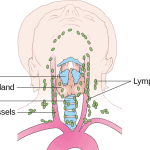

Introduction Examination of the neck is an important skills for assessing lumps and masses in the neck. Lumps in the neck are most commonly caused by the thyroid gland or…